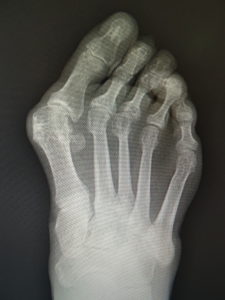

手術前 手術後4年

手術前 手術後

真田理事長による手術の様子。外反母趾|症例 (左から 手術前、手術後、ワイヤ抜去後)